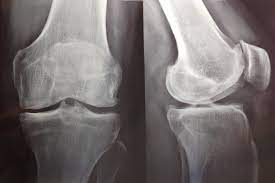

Variabilidad en la prescripción de fármacos con efectividad incierta. El caso de SYSADOA en el País Vasco.

GMS Health Technol Assess 2018 La incertidumbre en torno a estos medicamentos podría reflejarse en la variabilidad existente de su nivel de prescripción. El análisis de la variabilidad en la prescripción de medicamentos sin eficacia demostrada podría ayudar a asignar recursos a otros servicios o tecnologías de salud respaldados por evidencia, contribuyendo así a la mejora de los resultados de salud.